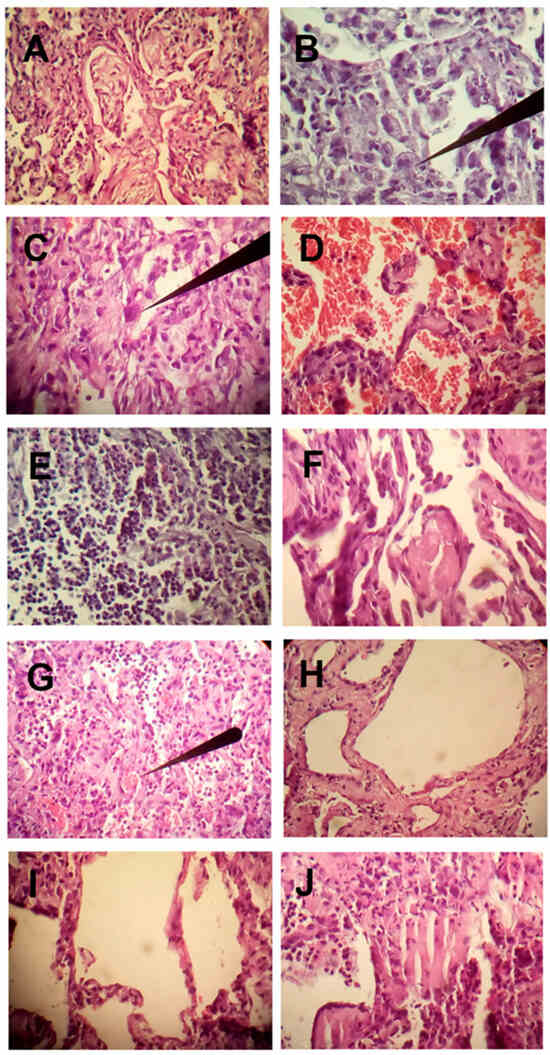

The histopathological findings of 19 patients who died from severe pneumolysis resulting from COVID-19 and adult respiratory distress syndrome in the intensive care unit of the General Hospital of Ecatepec, of the Health Institute of the State of Mexico, Mexico, are presented as preliminary findings (Figure 5). The time from initiation of mechanical ventilation to death averaged 16 days. Ultrasound-guided lung biopsies were performed immediately postmortem. The most important manifestation at the time of death, in addition to refractory hypoxemia, was CO2 retention (hypercapnia), with an average arterial blood gas CO2 of 90 mmHg (torr), confirming the pathophysiology (Figure 6 at sea level and Figure 7 at high altitude). Among the most important histopathological findings, as shown by the following photomicrographs, were changes associated with diffuse alveolar damage (DAD). This is a general term used in relation to ARDS [35], but since we are now dealing with a new highly lethal pathology, a more precise terminology is required. This is what we define as pneumolysis, an inflammatory process characterized by lung tissue derangement with alveolar collapse, hyaline tissue formation, microhemorrhages, microabscesses possibly due to superinfection, infiltration of polymorphonuclear cells and monocytes, and a repair process with organizational changes in fibrinoid deposits, early fibroblastic interstitial fibrosis, and Masson’s bodies. Additionally, fibroblast proliferation and collagen deposition with intense septal and para-septal reparative fibrosis can be observed, which significantly thicken the alveoli and explain the decreased gas-exchange area and hypercapnia in pneumolysis. Other authors have found the virus only in the acute initial stage of lung compromise and not in the progressive late stage, where there was an immune response that possibly cleared the virus [36]. However, in our studies, the presence of reactive pneumocytes with nuclear atypia (nucleomegaly, hyperchromasia) is striking [28], indirectly indicative of active viral replication, even at the time of death. This is a very important observation, as it shows the pneumocytes, due to SARS-CoV-2 aggression, with RNA inoculation within and changing the metabolite production code to replicate itself. This means that either the emergency cellular condition gives rise to nuclear.

Figure 5.

(A) Masson bodies. Note the hyaline border fixed to the alveolar walls. (B) Intra-alveolar macrophages (arrow). (C) Alveolar coating cells with nuclear atypia, reactive pneumocytes, and reparative fibrosis (arrow). (D) Intra-alveolar hemorrhage. Presence of intra-alveolar and septal interstitial polymorphonuclear cells. Note the thickening of the intra-alveolar septum with moderate inflammatory infiltrates. (E) Intra-alveolar abscesses. (F) Fibrinoid deposits. (G) Microthrombus (arrow). (H) Intense septal fibrosis. Note, in the lower part of the larger alveoli, the presence of a remnant of a hyaline membrane. (I) Area of alveolar rupture (emphysema). (J) infiltrated by pneumocystis (opportunistic infection). Photo and pathological analyses were performed by Dr. Felipe de Jesus Montelongo (Head Intensive Care) and Dr. Manuel Gabriel Romo Sanchez (Pulmonary Pathology specialist) from the Hospital General de Ecatepec Las Americas, ISEM, México.

Alterations or the virus itself alters the nuclei, which needs to be further investigated. The replication process is carried out in the lysosomes, the endoplasmic reticulum, and the Golgi complex [37]. Likewise, there are heterogeneous areas of alveolar rupture. These changes were observed in 100% of patients. Other findings included intra-alveolar hemorrhage in 54% of the patients and microabscesses by bacteria, fungi, and other opportunists such as pneumocystis in 50% of the patients, a finding of great importance since it was thought that most of the patients had died from pneumonia associated with mechanical ventilation. Likewise, microthrombi were found in 37% of the patients, which is not consistent with previous studies. It should be noted that 100% of the patients had prophylactic anticoagulation at the time of death.

We can conclude that the patients presented an active process of cell destruction (pneumolysis) due to active viral replication, with persistent infiltration of inflammatory cells and a continuous repair process but with reactive fibrotic activity that was so intense that it ultimately led to death. Furthermore, these multiple findings, with superimposed opportunistic infections, complicated the evolution of the disease.